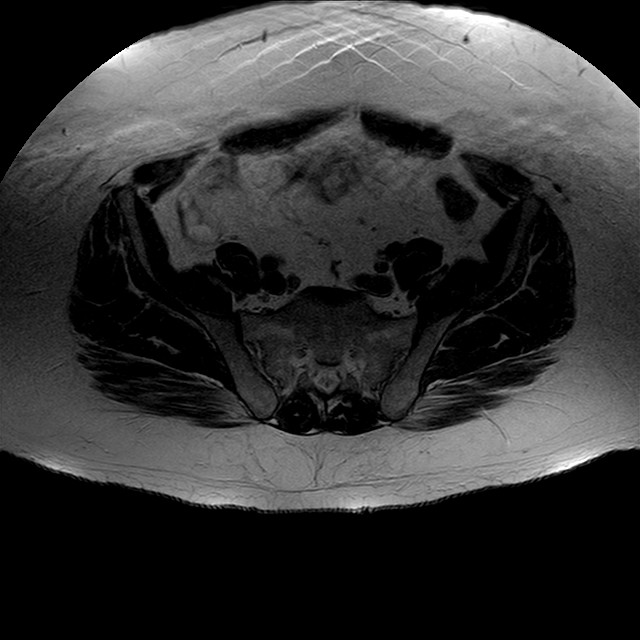

Esami: RMN BACINO

eT2w TSE

Evidenti e simmetriche alterazioni osteofitosiche in regione coxo femorale con riduzione delle rime articolari. Degenerazione completa del cercine glenoideo. Non attuali segni di versamento articolare. Non segni di edema osseo che escludono attuale algodistrofia od osteonecrosi. Lieve e simmetrica riduzione del trofismo della muscolatura glutea.